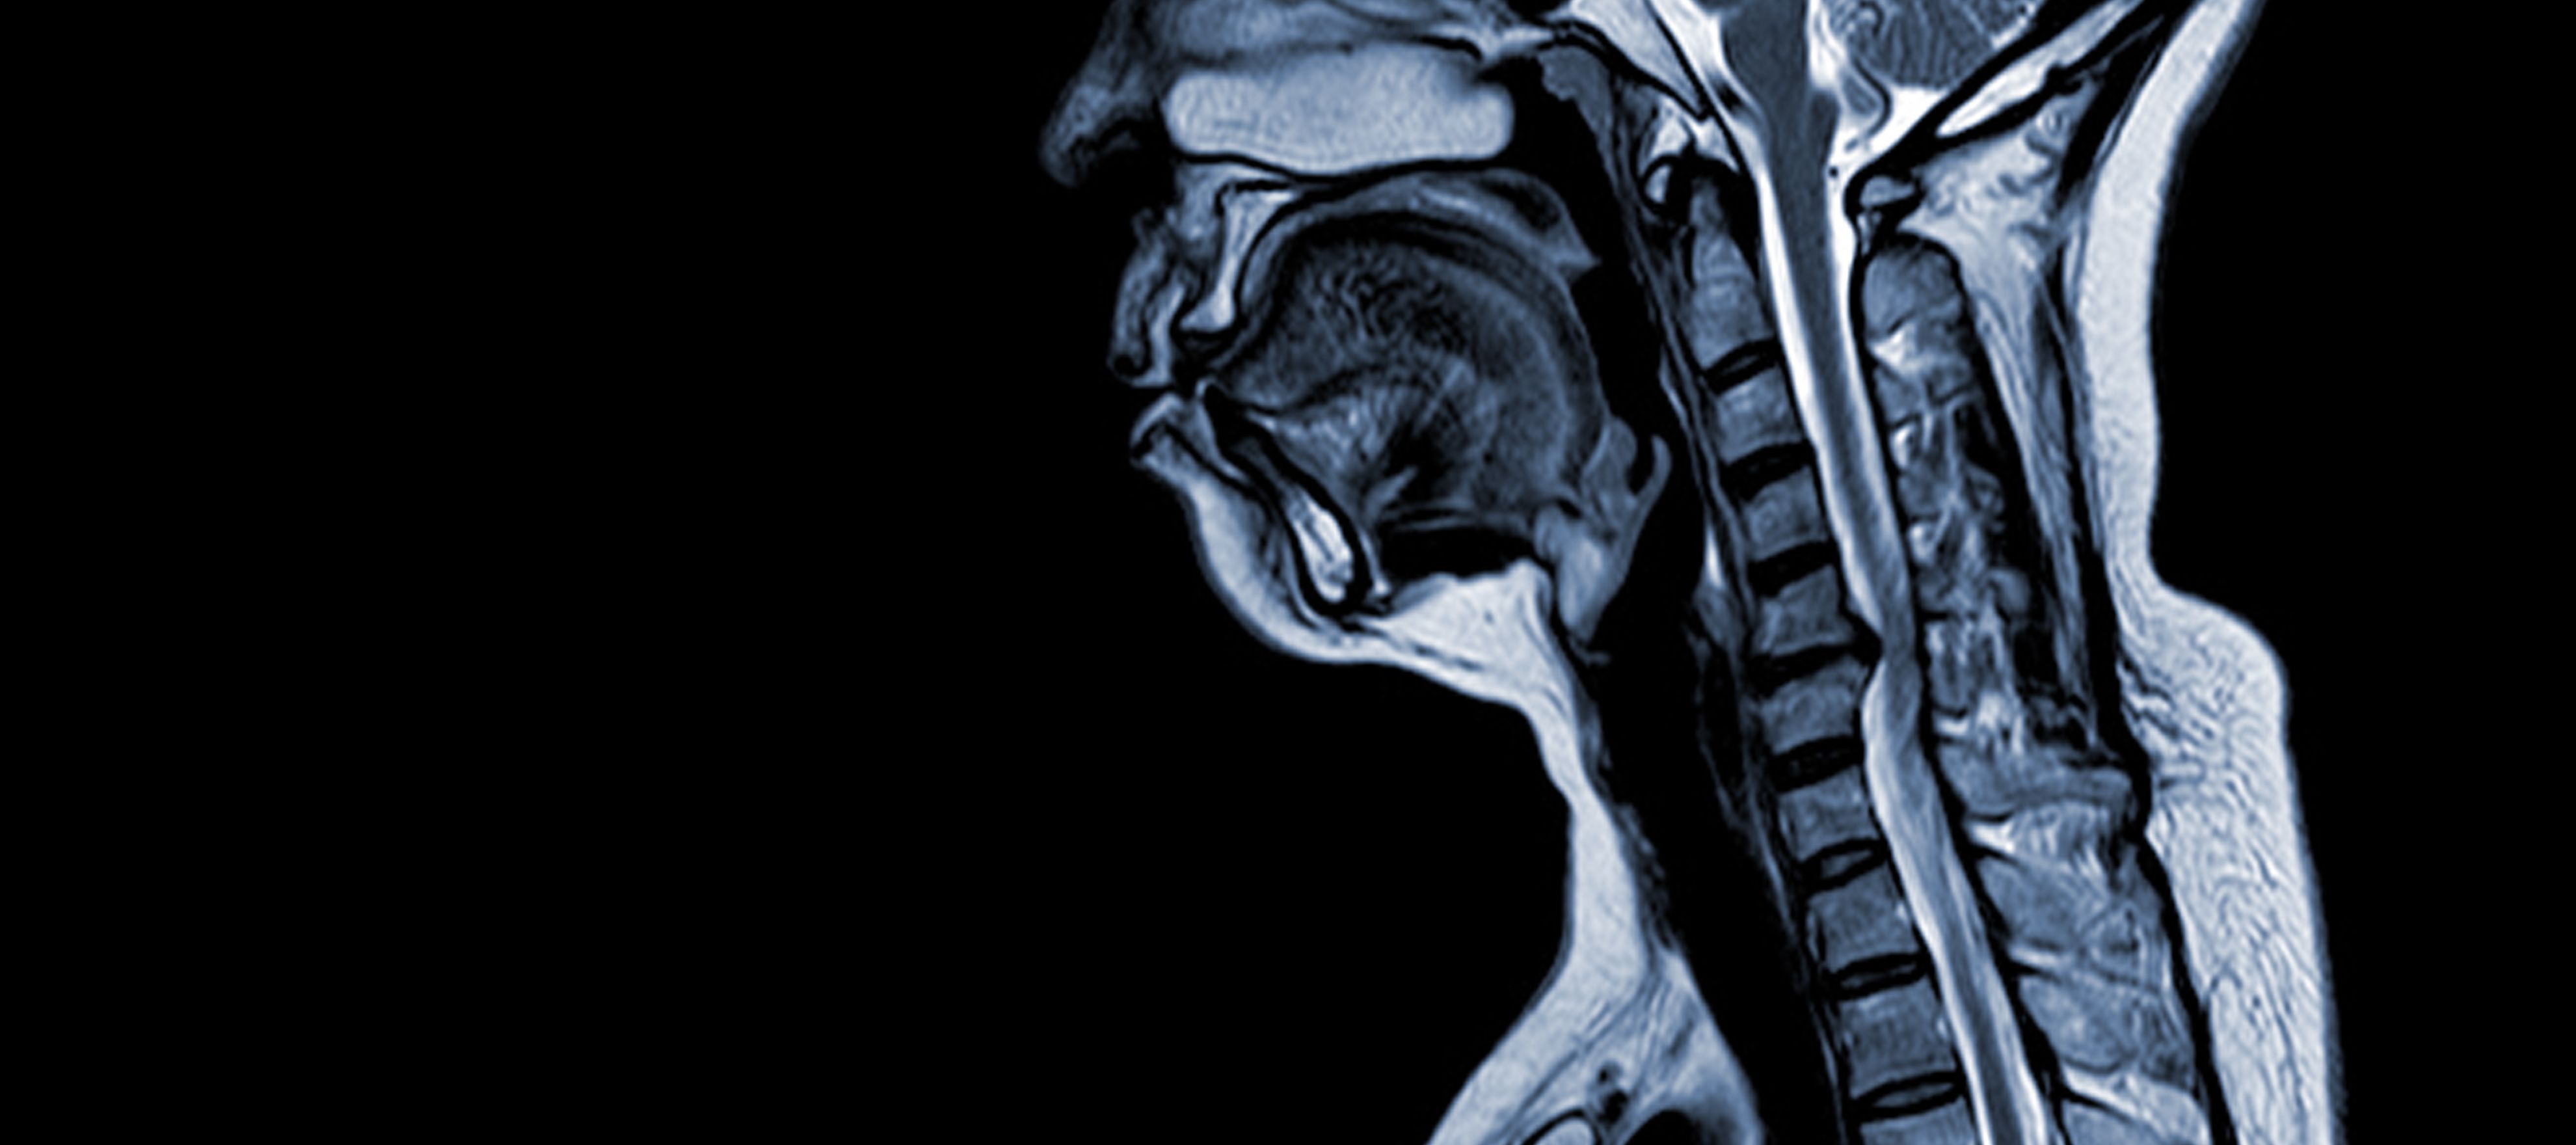

Cervikálna spondylotická myelopatia (CSM) je neurologické ochorenie, ktoré je hlavnou príčinou poranenia miechy u dospelých. Zjednodušene povedané, ide o stlačenie alebo poškodenie miechy na krku, predovšetkým v dôsledku prirodzeného procesu starnutia, ktorý postihuje krčné stavce. Pojem "myelopatia" pochádza z gréckych slov "myelon", čo znamená "miecha", a "pathos", čo znamená "choroba".

- Degenerácia disku (vypuklý disk): CSM sa často začína degeneráciou medzistavcových platničiek v krčnej chrbtici, čo spôsobuje ich vyklenutie alebo vysunutie do chrbticového kanála.

- Subperiostálna kostná formácia (ventrálne od spinálneho kanála): V reakcii na zvýšené mechanické namáhanie telo vytvára nové kostné tkanivo na prednej (ventrálnej) strane chrbticového kanála, čo môže zúžiť priestor pre miechu.

- Osifikácia zadného pozdĺžneho väzu: Zadný pozdĺžny väz môže podliehať osifikácii, stvrdnutiu a kalcifikácii, čo prispieva k zúženiu spinálneho kanála.

- Hypertrofia ligamentum flavum: Hypertrofia ligamentum flavum spôsobuje jeho zhrubnutie a zníženie pružnosti, čím ďalej zasahuje do priestoru v spinálnom kanáli a stláča miechu.

Tieto štrukturálne zmeny spoločne vedú k útlaku a zúženiu chrbticového kanála, čo vedie k charakteristickým príznakom a komplikáciám spojeným s CSM. Rozpoznanie týchto rizikových faktorov a pochopenie patofyziologických mechanizmov je nevyhnutné pre prevenciu aj liečbu. Včasná diagnóza a vhodné intervencie sú nevyhnutné na zmiernenie účinkov týchto štrukturálnych zmien na miechu.